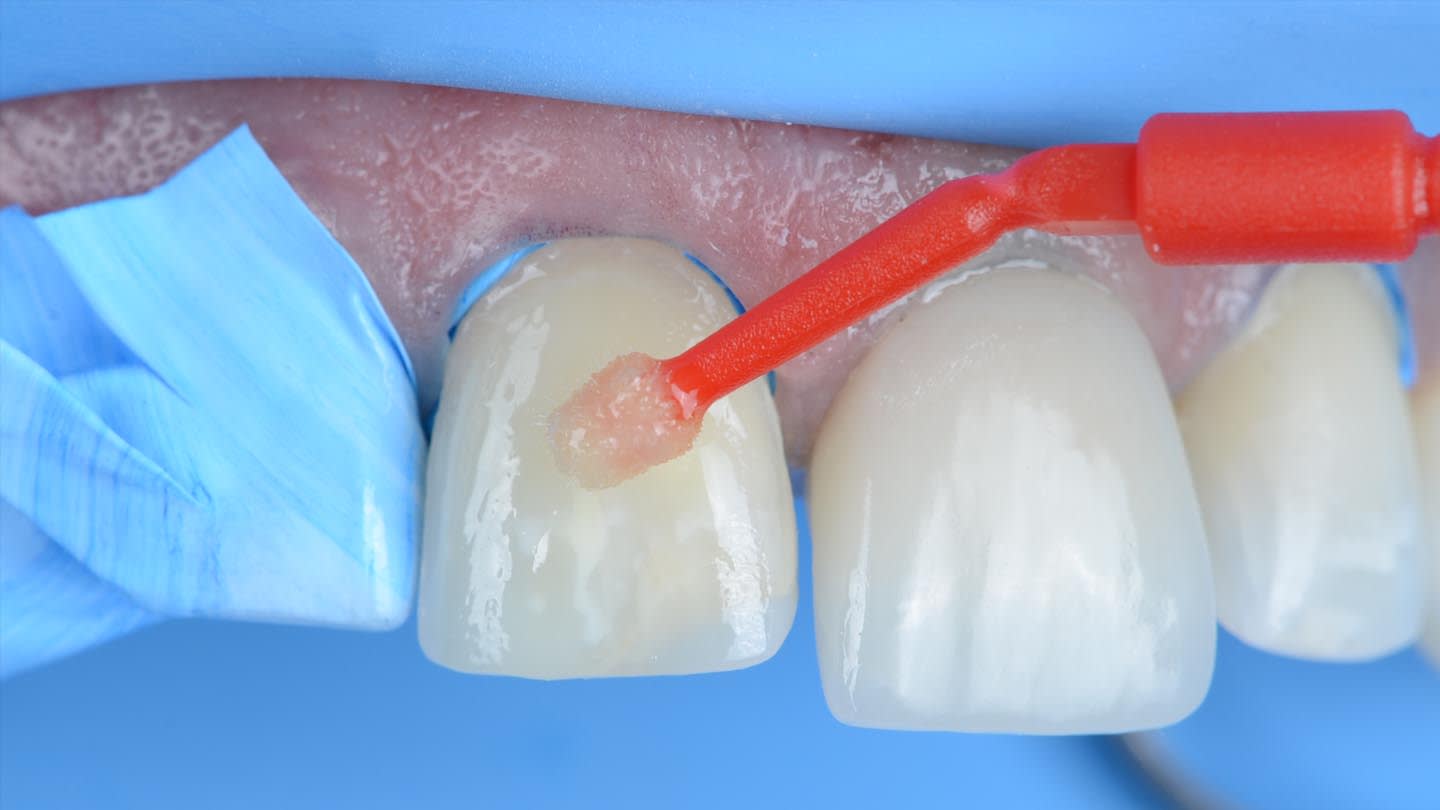

Rubber dam was used when bonding the final restorations. The veneer corresponding to tooth No. 9 was initially bonded to the opaque-core crown extraorally following standard protocol for silica-based ceramics,19 which included 9% hydrofluoric acid-etching (Porcelain Etch, Ultradent, ultradent.com), silane application (Monobond Plus®, Ivoclar), and application of a light-curing resin cement (Variolink® Esthetic LC, neutral shade, Ivoclar) (Figure 9 through Figure 13).

Next, the combined restoration was inserted into tooth No. 9 intraorally using a self-curing resin cement (Multilink Automix®, opaque white, Ivoclar) according to the manufacturer’s instructions. The try-in paste was always used prior to cementation to help predict the influence of the resin cement shade on the definitive restorations. For this case, white opaque cement exhibited good masking ability, especially in the cervical area. The remaining veneers were bonded with the same light-curing resin cement used in the initial bonding stage for tooth No. 9. A neutral shade was used to avoid influencing the final color of the restorations (Figure 14 through Figure 17).